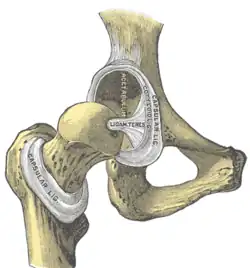

Teste de Ortolani ou manobra de Ortolani é um teste realizado no exame físico para investigação de displasia de quadril em recém-nascidos. Também é utilizado na medicina veterinária.

A Manobra de Ortolani consiste na flexão dos membros inferiores seguida da abdução da coxa para pesquisa de luxação congénita da anca/displasia de quadril. Na existência de uma displasia de quadril, ocorre um estalo (o sinal de Ortolani).